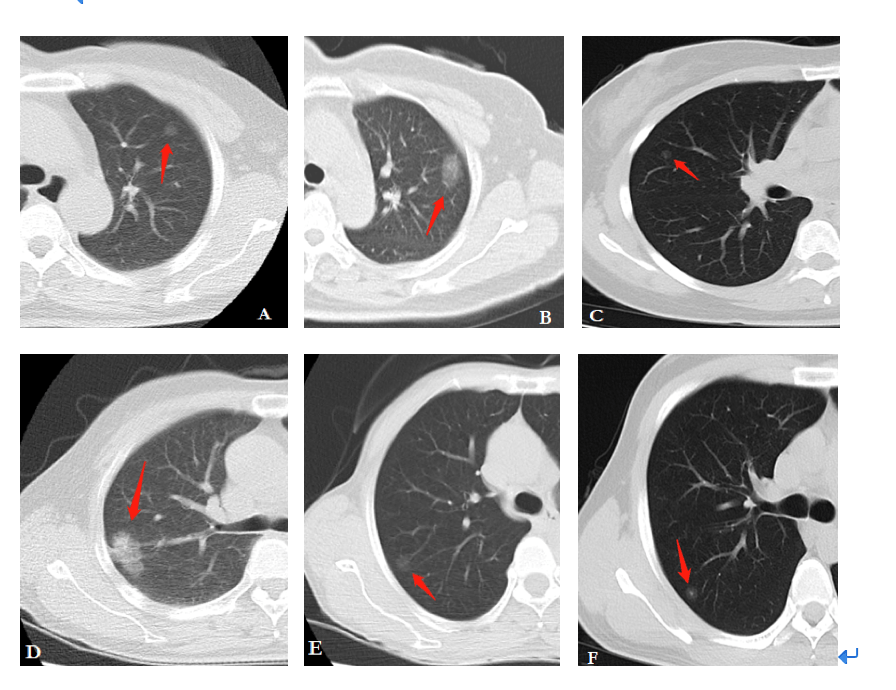

低剂量螺旋CT影像

低剂量螺旋CT是用最小的扫描范围,最低剂量,最少的X线量,对病变作出诊断。因为螺旋CT,常规一次扫描辐射量大概是3-5mSv,低剂量大概是1mSv,辐射量可以缩小2/3,对病变的检查也可以作出准确的诊断。相比传统的常规CT检查,一个是剂量小,使病人受到辐射小,对微小结节也能够清楚地显示。如果是在正规公立医院做检查,价格一般在300元左右。